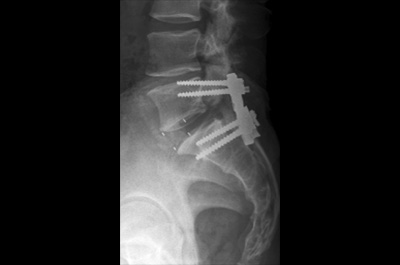

고령 및 심혈관계질환으로 전신마취와 수술 위험도가 높은 환자의 시술 사례

고령 및 심혈관계질환으로 전신마취와 수술 위험도가 높은 환자의 시술 사례 고령 및 심혈관계질환으로 전신마취와 수술 위험도가 높은 환자의 시술 사례

▲ 척추관 협착증

척추 디스크 나사 치료 척추 디스크 나사 치료

▲ 디스크를 제거하고 빈 공간에 케이지 삽입 후 나사못으로 고정시키는 수술